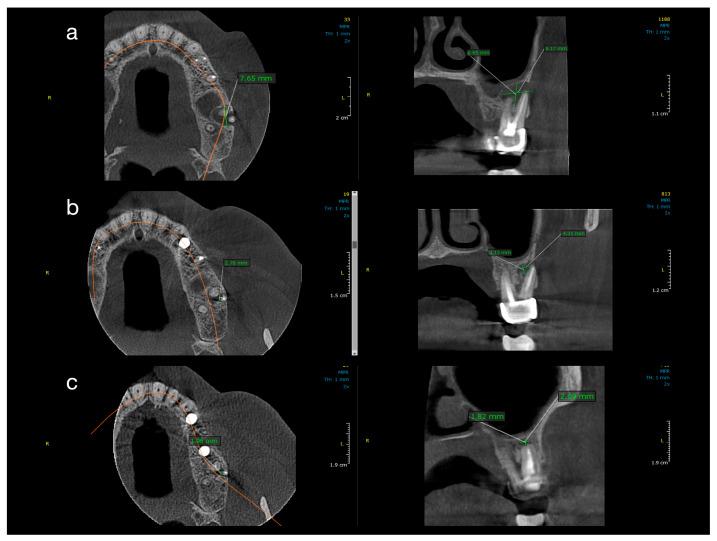

Large periapical cyst-like lesions pose challenges for nonsurgical management. This study evaluated the clinical and radiological outcomes of conventional endodontic therapy alone versus endodontic therapy with decompression in treating such lesions. Ten patients with CBCT-confirmed periapical lesions >5 mm were randomly assigned to two groups. Group 1 received standard root canal treatment with calcium hydroxide; Group 2 received the same protocol plus decompression. Lesion dimensions were measured in three planes using CBCT at baseline, 12 months, and 24 months. Both groups showed significant lesion size reduction over time. At 12 months, Group 2 had a significantly greater mean reduction (8.49 ± 5.09 mm) compared to Group 1 (4.36 ± 1.46 mm) ( = 0.008). At 24 months, both groups had comparable outcomes (Group 1: 1.12 ± 0.98 mm; Group 2: 2.41 ± 5.15 mm; = 0.356), with most lesions nearly or fully resolved. Histopathology confirmed radicular cysts in decompressed cases. Conservative endodontic therapy is effective for large periapical lesions. Adjunctive decompression accelerates early healing, particularly in extensive cases, potentially reducing the need for surgical intervention. CBCT is valuable for monitoring healing.

大型根尖周囊肿样病变给非手术治疗带来了挑战。本研究评估了单纯常规根管治疗与根管治疗联合减压治疗此类病变的临床和影像学结果。10例经CBCT确诊根尖周病变>5 mm的患者被随机分为两组。第1组接受氢氧化钙标准根管治疗;第2组接受相同方案加减压治疗。在基线、12个月和24个月时使用CBCT在三个平面测量病变尺寸。两组病变大小均随时间显著减小。在12个月时,第2组的平均减小幅度(8.49±5.09 mm)明显大于第1组(4.36±1.46 mm)(P = 0.008)。在24个月时,两组结果相当(第1组:1.12±0.98 mm;第2组:2.41±5.15 mm;P = 0.356),大多数病变几乎或完全消退。组织病理学证实减压病例中有根尖囊肿。保守的根管治疗对大型根尖周病变有效。辅助减压可加速早期愈合,尤其是在广泛病变的情况下,可能减少手术干预的必要性。CBCT对监测愈合很有价值。